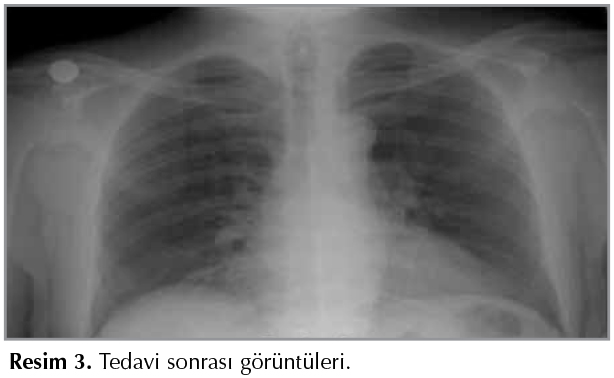

Elli altı yaşında erkek hasta; bir aydır olan nefes darlığı, 15 g?nd?r olan ?ks?r?k ve sarı renkli balgam, iki g?nd?r olan ateş ve miyalji şikayetiyle başvurdu. ?z ge?mişinde hipertansiyon, diyabet, 15 yıldır ankilozan spondilit (AS) ?yk?s? mevcuttu. Hastanın infliksimab 400 mg 4 yıl boyunca iki ayda bir kullanma ?yk?s? mevcuttu. İnfliksimab yanıtsızlık nedeniyle 50 mg/hafta etanersept kullanımına ge?ilmiş, 10 ay s?reyle tedavi g?rmekteydi. 2011 yılında t?berk?lin cilt testi 23 mm bulunması sonucu 9 ay s?reyle INH profilaksisi almıştı. Fizik muayenede; genel durumu orta, bilinci a?ık, koopere ve oryante idi. Solunum sistemi muayenesinde solunum seslerinda sağ bazal raller? mevcuttu. Diğer sistem muayeneleri doğaldı. Periferik sat?rasyonu %92 idi, solunum sayısı 30/dk idi. Postero-anterior akciğer grafisinde; sağ sin?s k?nt, sağ diyafragma ?st?nde diyafragmadan perifere uzanan atelektazi ile uyumlu lineer opasite, sol plevral ef?zyon, sol orta bazal parakardiyak opasite mevcuttu (Resim 1).

Resim 1